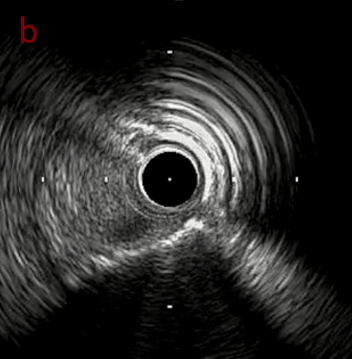

IVUS after OAS high speed 3回

IVUS imaging after high speed 3回

a,b,cはさらに石灰化に食い込み、石灰化量は減少。

それに伴いdではbiasがさらにtentingのIVUS所見にへんかしhigh injury riskと思われた。

引き続き造影で確認してpinpointで引きのOAS high speedを3回さらに追加のためcでIVUSマーキングを行い、その点より引きで赤線のpinpoint OAS high speedを行い、dに関してはinjury回避のためにOASを当てない方針とした。